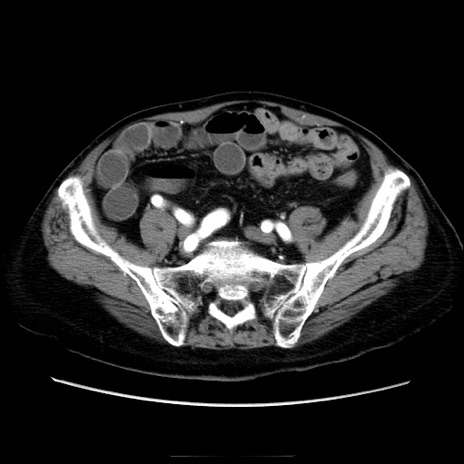

症例21(横断像)

【症例】70歳代男性

【主訴】腹痛

【現病歴】肝硬変・肝細胞癌にてかかりつけの方。約9時間前に食後より腹痛出現。症状が徐々に増悪し、嘔吐出現したため来院。

【既往歴】肝硬変、肝細胞癌(RFA、TACE後)

【身体所見】意識清明、表情苦悶様、BT 36℃、BP 129/78mmHg、P 88bpm、SpO2 97%(RA)、右上腹部から心窩部にかけて圧痛あり、反跳痛なし、筋性防御あり。

【データ】WBC 5800、CRP 0.16